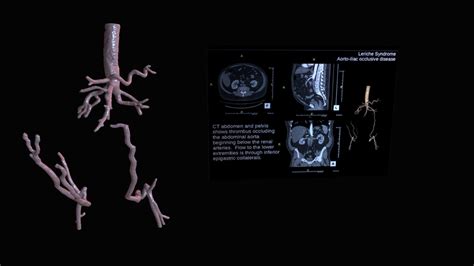

Aortoiliac Occlusive Disease (AIOD), often referred to as Leriche syndrome when it involves the complete occlusion of the distal abdominal aorta, represents a severe form of peripheral artery disease (PAD). This condition occurs when the iliac arteries—the major vessels that branch off the abdominal aorta to supply blood to the lower extremities—become narrowed or blocked due to the accumulation of plaque. Because these vessels serve as the primary "highway" for oxygen-rich blood traveling to the legs, any obstruction can lead to debilitating symptoms, ranging from intermittent claudication to critical limb ischemia. Understanding the nuances of this condition, from early warning signs to modern intervention strategies, is vital for maintaining cardiovascular health and mobility.

At its core, Aortoiliac Occlusive Disease is a manifestation of atherosclerosis. Over time, fatty deposits, cholesterol, and other cellular waste products build up on the inner walls of the arteries. This narrowing (stenosis) or total blockage (occlusion) creates a high-resistance environment for blood flow. As the heart pumps blood to the lower body, the reduced cross-sectional area of the aorta and iliac arteries forces the body to compensate through collateral circulation, which is often insufficient to meet the metabolic demands of the muscles during physical activity.

CTA / MRA Anatomic mapping Provides detailed 3D images of the aorta and iliac bifurcations.